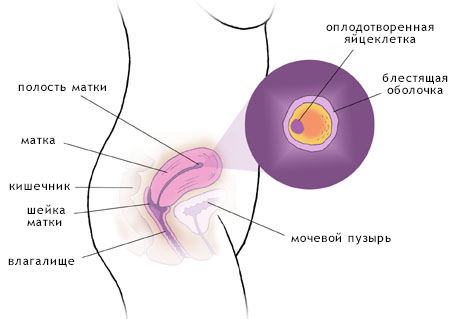

Другий тиждень - це термін, на якому майбутня дитина прикріплюється до матки. У цей період часто відбуваються викидні, причому якщо жінка про свою вагітність не знає, то викидня вона цілком може не відчути.

Якщо розглядати це питання з наукової точки зору, то фолікула в цей час продовжує свій розвиток в яєчнику, таким чином виділяється жіночий гормон - естроген. Це є причиною збільшеного статевого потягу на другому тижні. При повному дозріванні фолікул в діаметрі досягає двох сантиметрів. Усередині фолікула збільшується кількість рідини, через це він лопає і недозріла гамета виходить назовні.

Саме в цей проміжок часу, поки яйцеклітина діюча, її можливо запліднити, в такому випадку настає вагітність.

Друга акушерська тиждень є початком ембріонального періоду, який і буде тривати наступні дев'ять місяців. Саме з цього часу майбутня матуся починає помічати в своєму тілі зміни, також змінюватися починає її настрій. Жінці завжди цікаво, що ж відбувається всередині неї, це природно, так що на цьому етапі вона, як правило, починає борознити простори Інтернету в пошуку докладного опису всіх процесів, які відбуваються в той чи інший період вагітності.